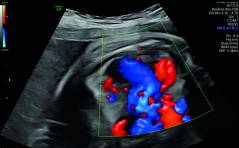

Sonoquiz

Was ist das? PDF Dokument

Auflösung Sonoquiz

Vorzeitige, partielle Plazentalösung PDF Dokument